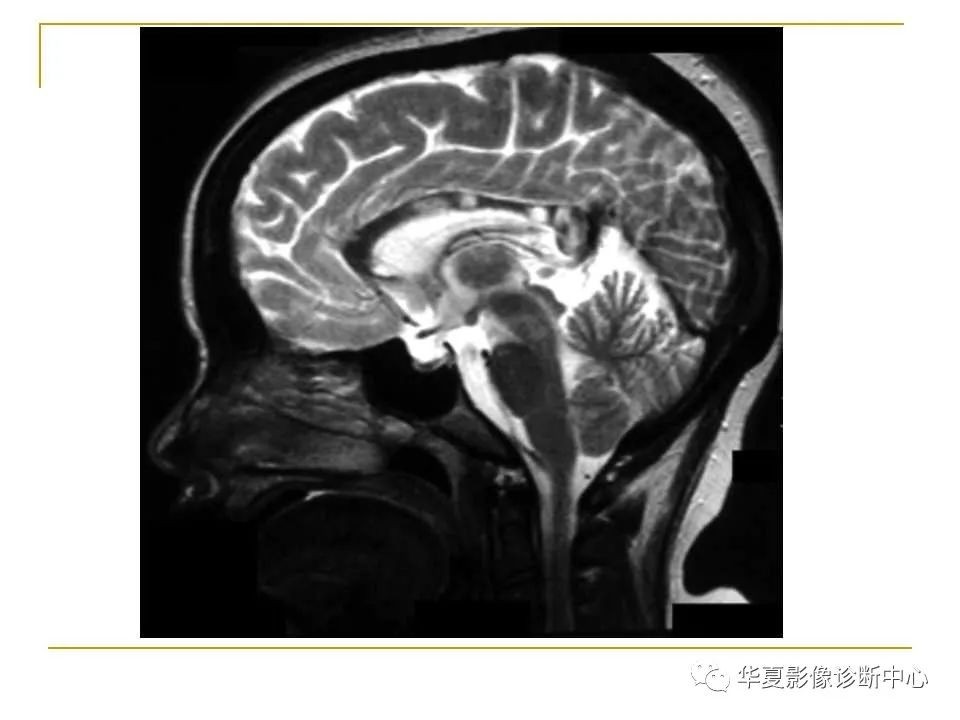

胼胝体解剖及病变大全